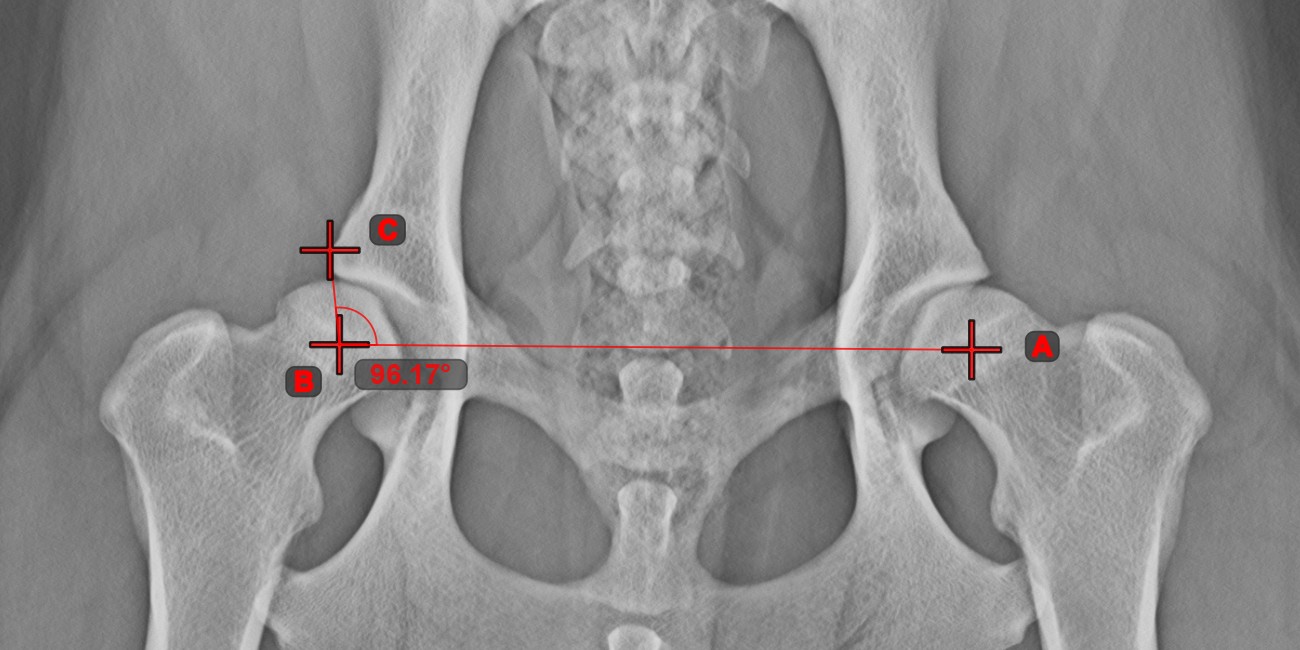

Szög 3 pontból¶

A Szög 3 pontból eszköz egyszerű és hatékony módja annak, hogy egy szöget mindössze három pont alapján számítson ki.

Kezdje az eszköz kiválasztásával a bal oldali eszköztárból, és rendelje hozzá az egyik elérhető egérgombhoz. Helyezze el a szög kezdeti oldalának kezdőpontját, a csúcsot és a szög végoldalának végpontját, vagy válassza ki a pontokat a jelenetből. A szög oldalai automatikusan létrejönnek, így a vonalak közötti szög kiszámításra kerül.

Módosítsa a három pont helyzetét a szög ívének megváltoztatásához az Elem kiválasztása/mozgatása eszközzel.